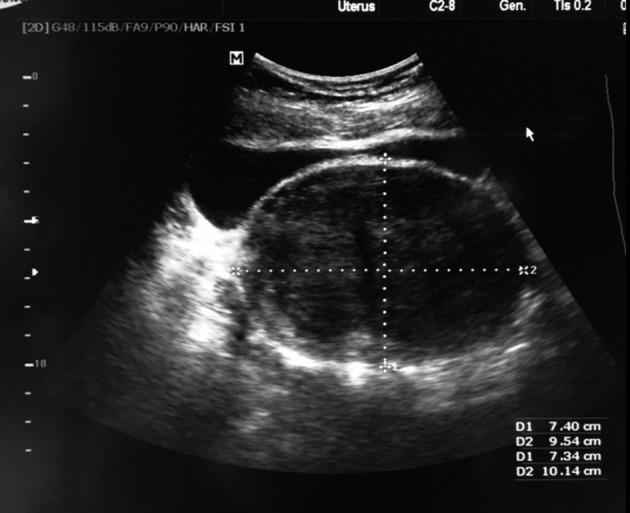

The occurrence of an extra-uterine leiomyoma, arising from the intra-peritoneal portion of the round ligament in a lady with Müllerian agenesis diagnosed at the age of forty is extremely rare. We report a case of this rare combination in a Middle Eastern woman.

CASE

A 40 years old lady, primarily amenorrheic, presented to our clinic for an infertility consultation. The work- up showed features suggestive of Mayer-Rokitansky-Küster-Hauser (MRKH) syndrome with a leiomyoma arising from the intra-peritoneal part of the round ligament.

一名40岁被诊断为苗勒氏管发育不全的女性,其圆韧带腹膜内部分出现子宫外平滑肌瘤的情况极为罕见。我们报告了一名中东女性的这种罕见病例组合。

病例

一名40岁的女性,原发性闭经,因不孕症前来我们诊所咨询。检查显示有梅耶-罗基坦斯基-库斯特-豪泽(MRKH)综合征的特征,同时伴有一个起源于圆韧带腹膜内部分的平滑肌瘤。